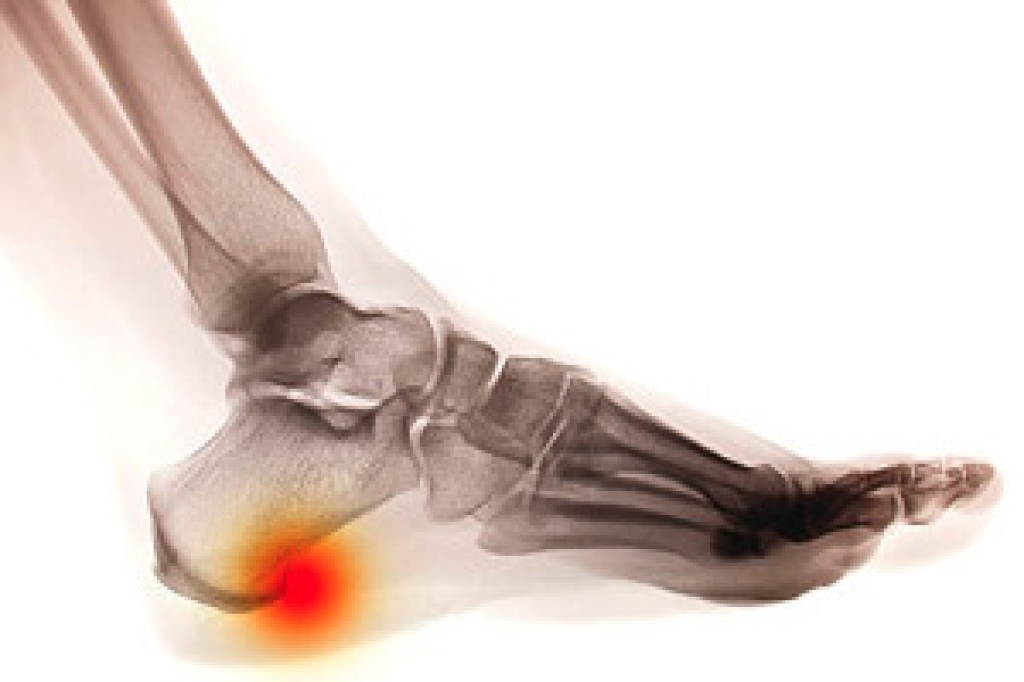

The ankle joint is the point at which the bones of the leg and foot join. This joint is crucial because it is responsible for the foot’s mobility. Ankle pain is typically the result of inflammation from an injury to bones, joint space, cartilage, ligaments, tendons, or muscles in the area. Commonly associated symptoms with ankle pain are bruising, redness, numbness, stiffness, weakness, and tingling.

The most common causes of ankle pain are sprains and injuries. Ankle sprains are one of the most common musculoskeletal injuries. Sprains occur when the ligaments of the ankle become partially or completely torn due to sudden stretching. Sprains can occur on either the inner or outer sides of the ankle joint. Usually, these injuries occur when the ankle is twisted in an activity by stepping off an uneven surface. More specific causes include rheumatoid arthritis, gout, osteoarthritis, and Achilles tendonitis.

Due to the wide variety of potential causes of ankle pain, podiatrists will utilize a number of different methods to properly diagnose ankle pain. This can include asking for personal and family medical histories and of any recent injuries. Further diagnosis may include sensation tests, a physical examination, and potentially x-rays or other imaging tests.